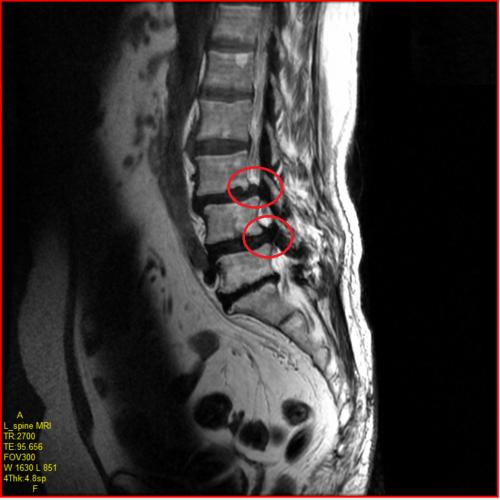

- 영상 검사: X선, MRI, CT와 같은 검사로 척추의 구조적 문제를 확인합니다. 이를 통해 신경이 얼마나 압박받고 있는지에 대한 정보를 제공합니다.

- 디스크 문제: 척추 사이에 위치한 디스크가 퇴화하거나 탈출하는 경우, 신경이 압박받아 협착 증상을 초래할 수 있습니다.